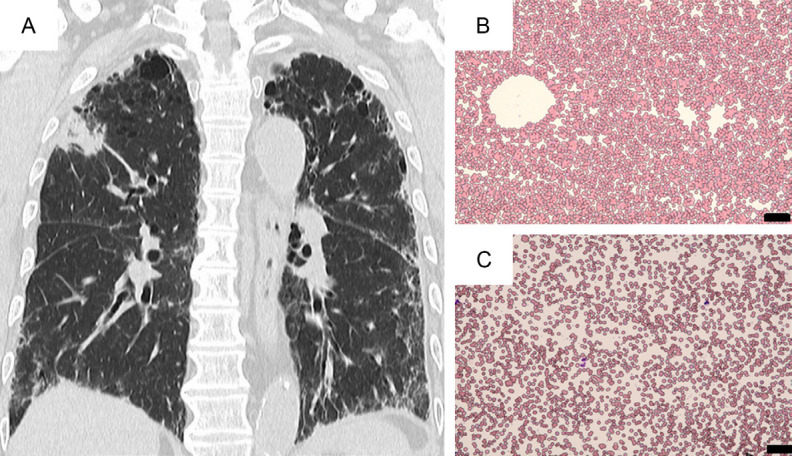

A 79-year-old man, afebrile, was hospitalized for undergoing a bronchoscopic examination to determine the pathology of an underlying pulmonary disease. He had been treated for his non-specific interstitial pneumonia (NSIP) for longer than 6 years, and for a right upper lung mass on CT that had been detected one year ago (Figure 1A). He was suspected of having either autoimmune pneumonia, lung IgG4-related disease, or lung carcinoma. He also had cervical adenopathy without cutaneous lesions. On admission, his laboratory data were WBC 9000/µL, Hb 12.3 g/dL, platelet count 46 K/µL, and CRP 0.52 mg/dL. Lactate dehydrogenase (LDH) 201 U/L, and normal hepatic/renal function. He was ANA-positive (×640). Tumor and other biological markers were CEA 4.82 (<5) ng/mL, Pro-GRP-S 45.2 (<81) pg/mL, CYFRA 2.7 (<3.5) ng/mL, SCC 1.3 (<1.5) ng/mL, MMP-3 55.1 (36.9-121), KL-6 1045 (<499), SP-A 60.1 (<43.5), and SP-D 144 (<110) ng/mL. The serum level of IgG was 1750 mg/dL with IgG4 of 103 mg/dL.

Figure 1.

CT of the chest (coronal axis) shows bilateral interstitial pneumonitis with a mass lesion at the right upper lung (A). At the time of CAD development, blood smear at room temperature demonstrated RBC agglutination (B), while after warming of blood at 36ºC, RBC agglutination resolved (C) (May-Giemsa staining; original magnification ×200, scale bar indicates 50 µm).

PET-CT revealed an FDG-avid 5.5 cm-sized mass (SUVmax=7.12) at the right lung, as well as enlarged lymph nodes at the bilateral supra-clavicular area (SUVmax=10.12), mediastinal (SUVmax=11.26), and pulmonary hilar lesions. Also, there were FDG-avid lymph nodes (SUVmax=5.42) at the bilateral cervical area and a mass (SUVmax=5.80) at the right parotid gland (Figure 2). Endobronchial ultrasound-guided transbronchial needle aspiration (EBUS-TBNA) of peri-bronchial lymph nodes revealed no malignancy. The resection of the left supraclavicular lymph node demonstrated the histology of RDD, showing the sinus expansion of large histiocytes with emperipolesis in the abundant pale eosinophilic cytoplasm, associated with coagulative necrotic lesions (Figure 3). Multinucleated giant cells were also noted. IgG4+ cells were scattered, but IgG4-related disease (IgG4-RD) was ruled out. Immunohistochemical staining of histiocytes showed S100 (+), CD68 (+), CD163 (+), OCT2 (+), but CD1a (-), CD3 (-), CD20 (-), MPO (-), AE1/AE3 (-), BRAF V600E(VE1) (-), pERK (-), ALK (-), panTRK (-) and Ki-67 (16%). The diagnosis was made as nodal RDD. However, the respiratory tract lesions were not confirmed to be extra-nodal RDD. After the diagnosis of RDD, we decided to observe the patient without specific therapy, because of his NSIP. However, within 3 months, he developed cold agglutinin disease (CAD) with a titer of ×128. Blood smear at room temperature showed marked RBC aggregates, and after warm-up at 38°C, RBC aggregates resolved (Figure 1B, 1C). Hemolytic anemia was significant (Table 1). A bone marrow smear revealed erythroid hyperplasia without light chain restriction by flow cytometry, and no B-cell lymphoproliferative disease was detected. The patient’s anemia has been treated with packed red blood cells (2 units ×3), and the administration of sutimlimab® (a humanized monoclonal IgG4 antibody that binds and inactivates complement protein C1s; 6.5 g/dose) [13] was planned. However, after a single administration, it was not possible to continue the treatment because the patient’s NSIP worsened. Thus, we could not evaluate the effectiveness of sutimlimab® in CAD. The patient eventually died of respiratory failure.